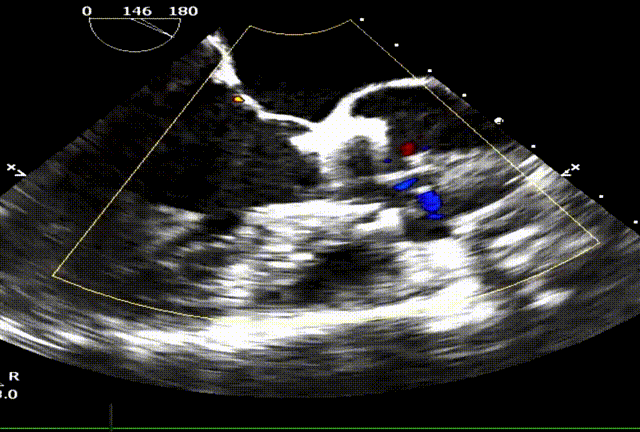

食道超声显示瓣架圆形展开,位置合适,未见显著反流:

台上复查食道超声,瓣架圆形展开,启闭良好:

食道超声瓣架位置正确,启闭良好,未见明显瓣周漏: